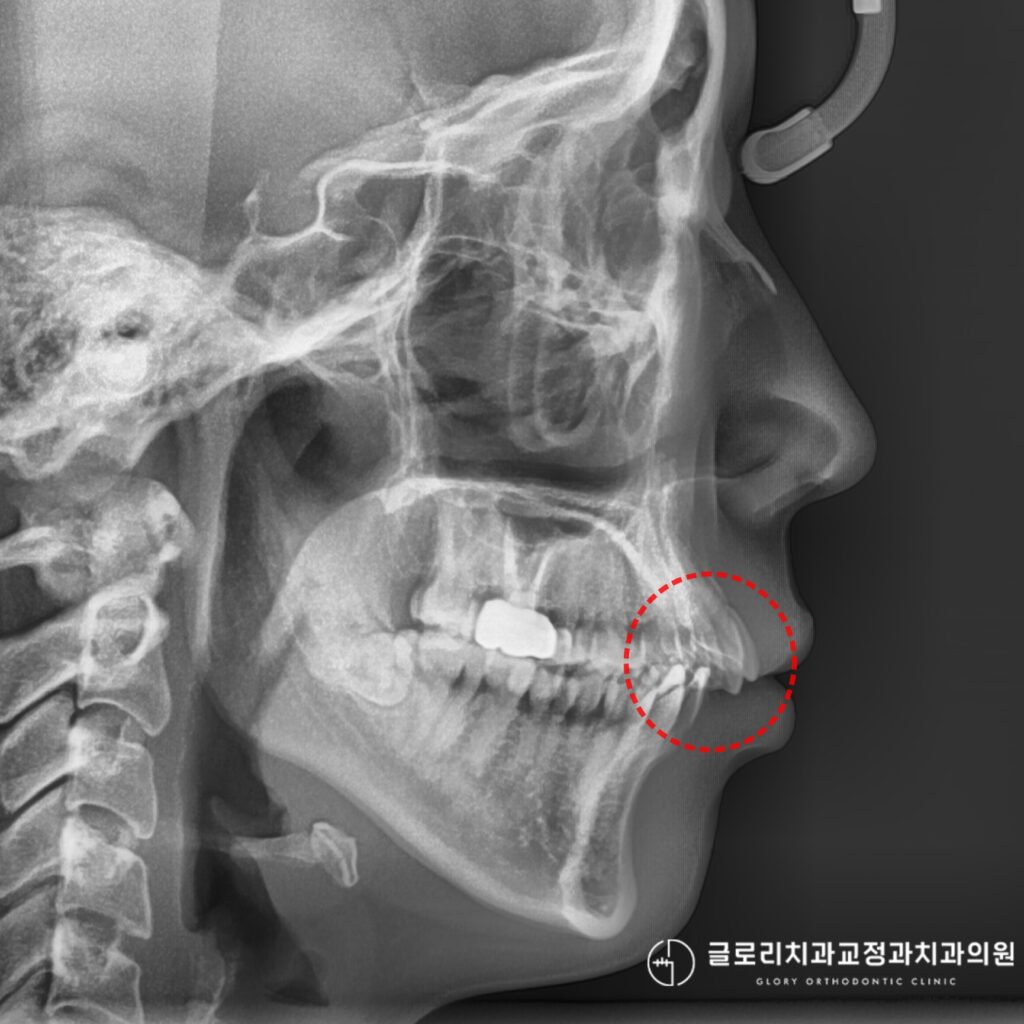

상악골확장 후 3차원 CT를 촬영해

뼈의 변화량을 확인하고

남은 공간을 계산하여

최종 치료 계획을 수립하게 됩니다.

봉합선의 골화 정도와

뼈의 두께, 비강 구조 등을

사전에 정밀하게 분석해야 합니다.

특히 성인의 경우

봉합선이 완전히 결합되어 있으면

확장이 어려울 수 있어

CT 검사를 통한 판단이 필수입니다.